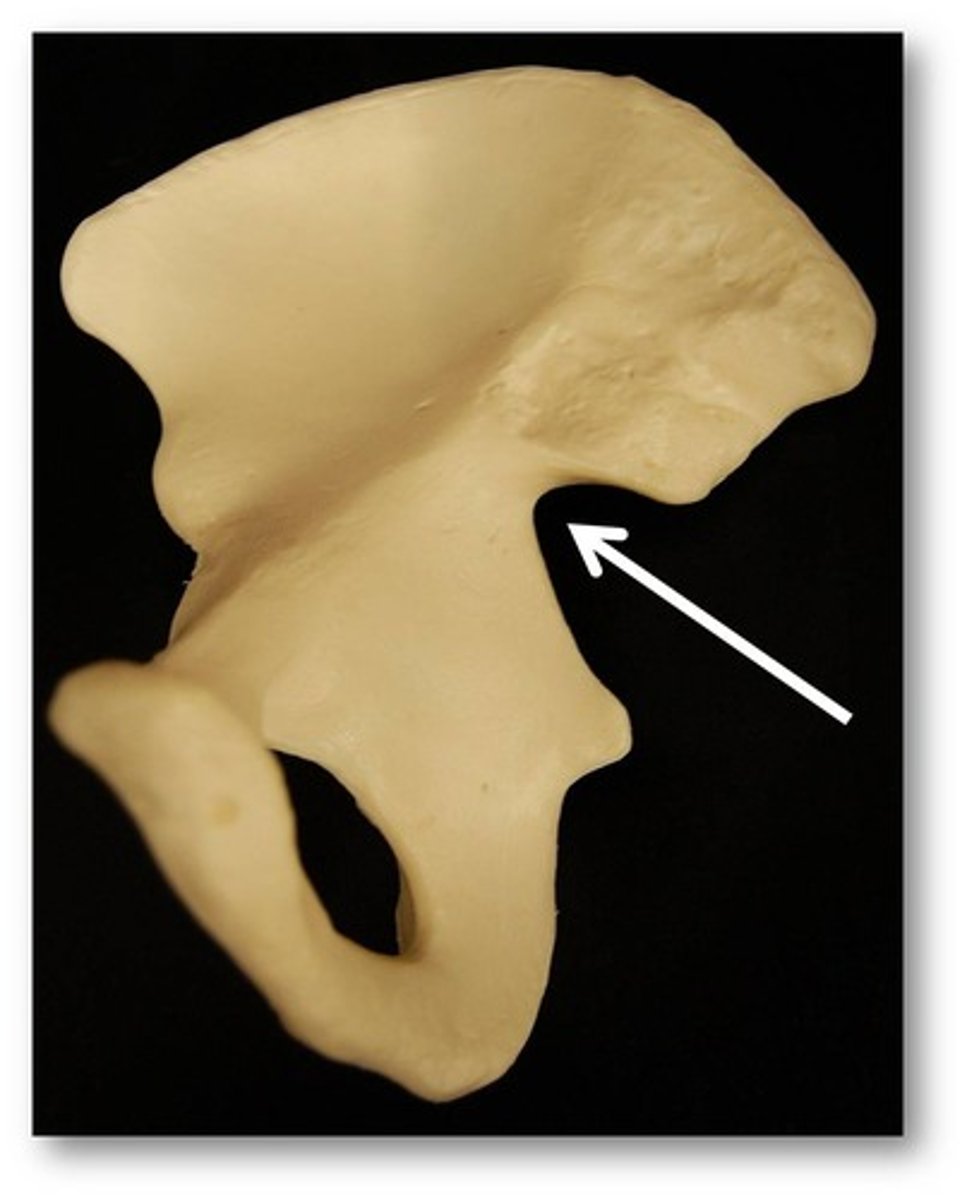

greater sciatic notch

allows blood vessels and the large sciatic nerve to pass from the pelvis posteriorly into the thigh